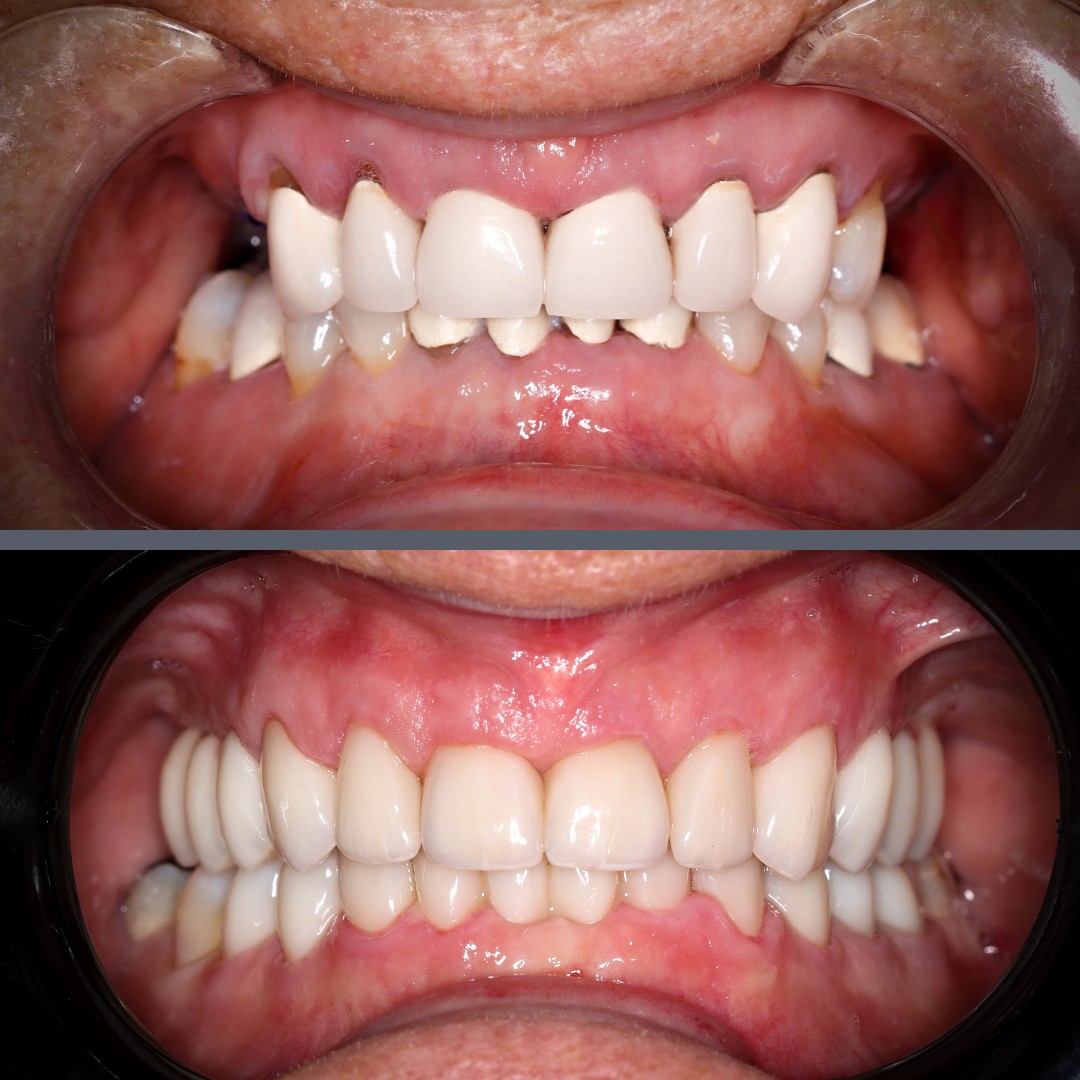

Missing teeth and aesthetic concerns – smile restored with implants and zirconia crowns

Nearly 70 and ready for a change, our patient came to us with multiple missing teeth and others that were aesthetically compromised. She was seeking a stable, long-lasting solution that would also look and feel natural. A complex, full-mouth rehabilitation involving both upper and lower jaws was necessary.

In the second stage, temporary crowns were fitted to ensure a natural appearance and to protect the implants during the healing process.

In the final restorative phase, we created a full set of permanent restorations for both arches. The missing teeth were replaced with zirconia crowns attached to the implants, while the patient’s remaining teeth were also restored with zirconia crowns. Zirconia is a metal-free material that combines exceptional durability with lifelike aesthetics – making it ideal for restoring both front and back teeth.

The patient’s smile was restored in function and appearance, resulting in a significant improvement in quality of life. She can now enjoy her favourite meals again and smile with confidence, knowing she has a long-lasting, reliable solution.